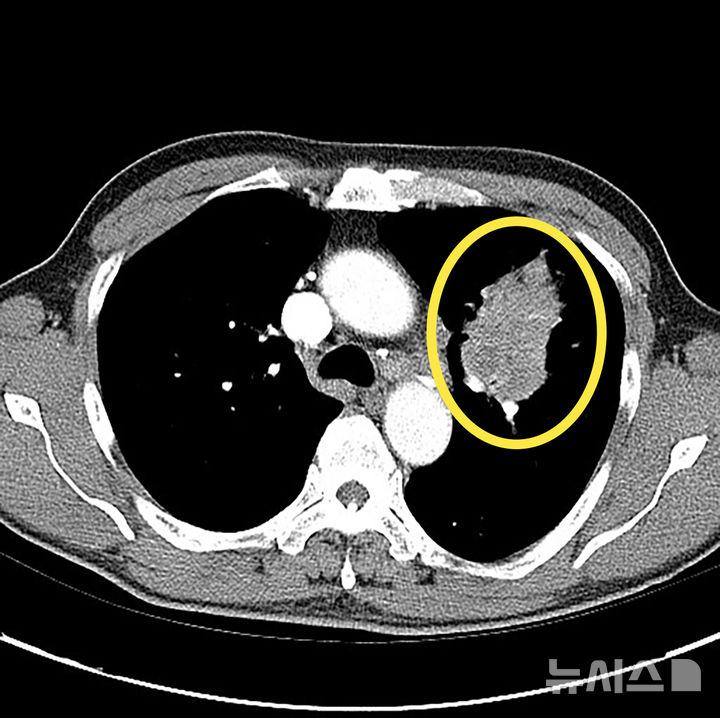

15일 의료계에 따르면 폐암은 폐에 비정상적인 암세포가 무절제하게 증식해 종괴(덩어리)를 형성하고 인체에 해를 미치는 것을 말한다. 폐암은 폐에 국한돼 발견되기도 하지만 진행될 경우 반대쪽 폐뿐 아니라 임파선이나 혈액을 통하여 뼈, 간, 부신, 신장, 뇌, 척수 등 온몸으로 전이될 수 있다.

하지만, 최근에는 비흡연자에게서도 폐암 발병이 증가하고 있어 증상이 없고 고위험군이 아니더라도 관심을 기울일 필요가 있다. 간접흡연이나 요리시 발생하는 연기, 라돈·석면 등 발암물질에 노출되는 직업 종사자나 미세먼지 노출시에도 폐암에 걸릴 수 있다. 저선량 흉부 CT(컴퓨터단층촬영)는 폐암 조기 진단에 매우 효과적인 수단으로 만성 폐쇄성 폐질환(CODP)이나 다른 암 병력이 있는 등 고위험군에서는 정기적인 검사가 권장된다. 저선량 CT는 환자에게 노출되는 방사선량을 6분의 1 수준으로 최소화한 장비다.

폐암이 조기 발견이 어려운 이유는 폐에는 감각 신경이 없어 통증을 잘 느끼지 않는 장기이기 때문이다. 실제 조기에 폐암이 진단되는 환자는 전체의 5~15%에 불과하다. 폐암이 진행되면 기침, 피 섞인 가래(객혈), 흉통, 호흡곤란, 체중감소 등이 나타날 수 있다. 하지만 이런 증상도 암이 꽤 진행된 후에야 나타나는 경우가 많아 증상만으로는 조기 진단이 어렵다. 증상이 나타났다면 이미 폐암이 어느정도 진행된 경우가 많다.

따라서 고위험군에서는 저선량 CT를 이용한 정기 검진이 매우 중요하다. 결절이 발견된다고 다 암으로 진행되는 것은 아니다. 결절은 암일 수도 있지만 염증, 섬유화, 림프절 비대, 과거 결핵 흔적 등 다양한 원인으로 생길 수 있다. 특히 폐암 고위험군이라면 호흡기알레르기내과 전문의에게 진료를 받아 정확한 평가를 받는 것이 필요하다.